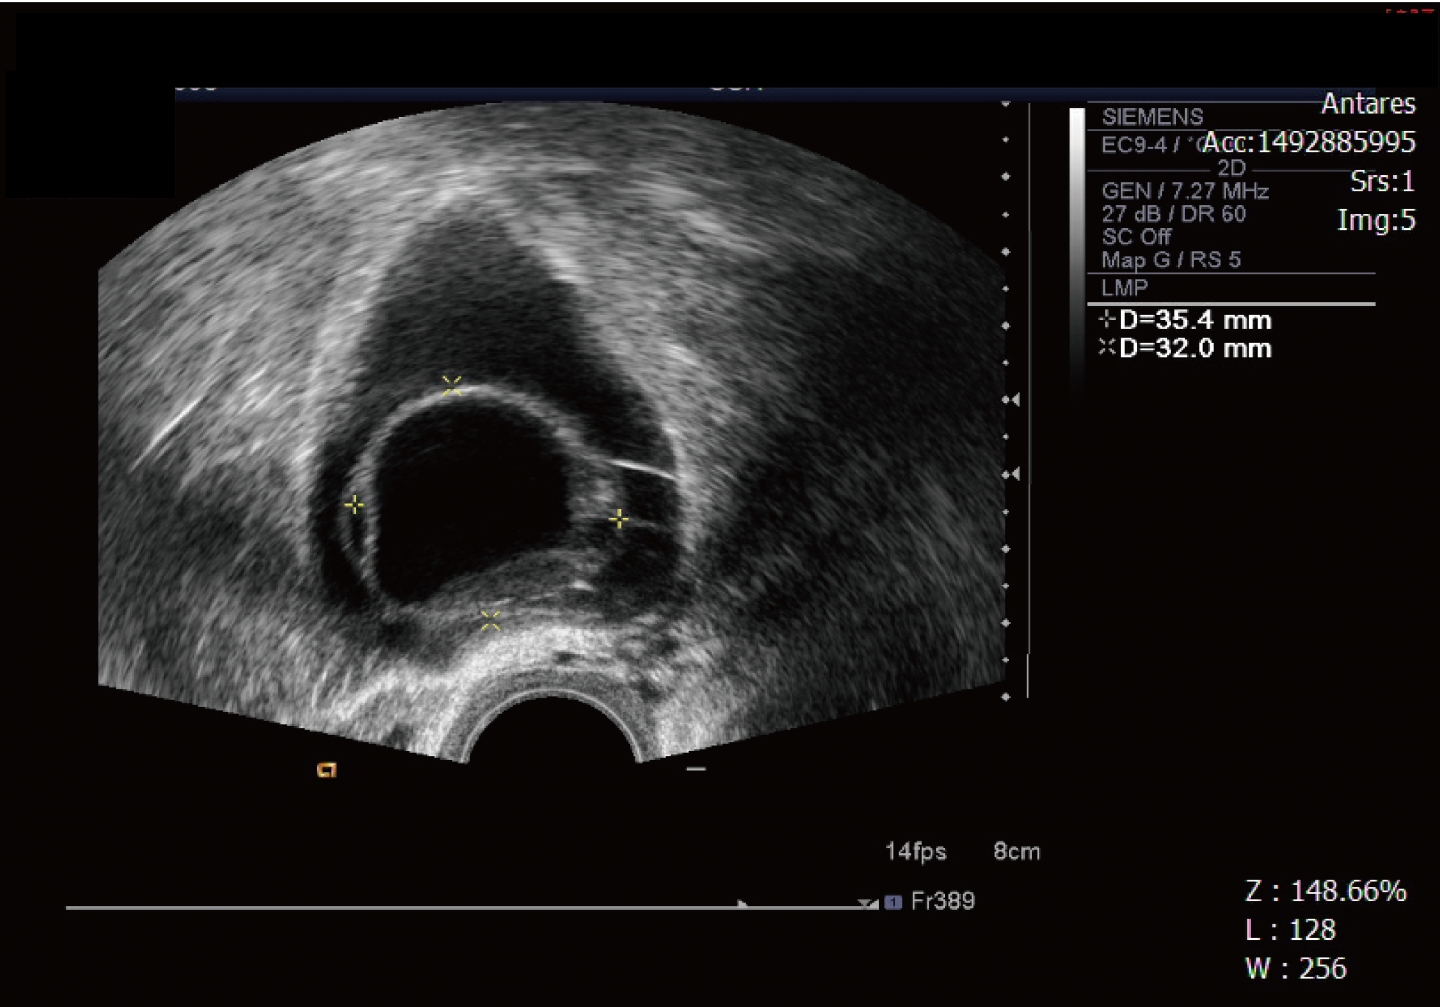

(當然後續超音波追蹤時,我還是非常擔心這個輸卵管能用嗎?)

這位患者再度接受腹腔鏡手術,不過這次手術對象是巧克力囊腫 這時的輸卵管已經比較正常,也在這個手術之後,她願意進入試管嬰兒療程。(正常的輸卵管樣子)